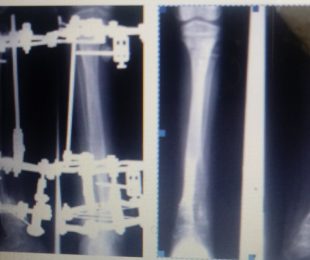

9 – Perdas Ósseas Segmentares

14- Fixação Externa nas Dismetrias dos Membros Inferiores

15- Pseudoartrose infectada

16- Pseudartrose umero= tratamento com a fixação externa de ILIzarov

Página 2 de 3